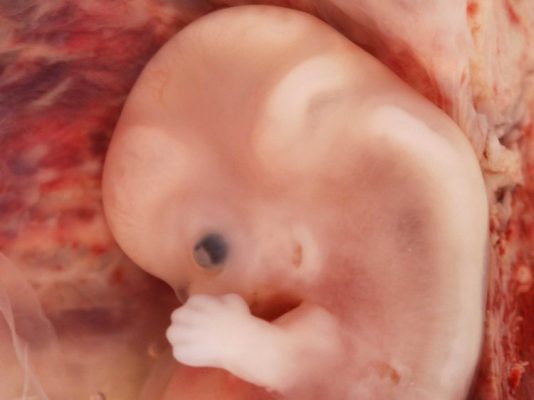

До 35-го дня клетки зародыша продолжают делиться и «специализироваться» – формируется 43–44 сегмента, из которых до конца второго месяца внутриутробного развития будут развиваться скелет и зачатки всех органов. На 8–9 неделе эмбрион уже напоминает человека, его вес составляет около 5 г, а рост – 40 мм.

На третьей неделе эмбрионального развития, что соответствует пятой неделе беременности, в области будущего позвоночника формируется канавка из эктодермы. Позже ее края сливаются, образуя нервную трубку, из которой впоследствии разовьются спинной и головной мозг. К концу этой недели размер эмбриона составляет около 4 мм.

На четвертой неделе из нервной трубки начинает формироваться основа центральной нервной системы — спинной и головной мозг. Сердце совершает свое первое сокращение. Появляются зачатки рук, ног, глаз и внутренних органов, а также начинается кровообращение.

В пятую и шестую недели происходит формирование головной части и черт лица эмбриона, его длина составляет примерно 1 см.

На седьмой неделе удлиняются конечности, и начинается развитие легких. Сердце уже полностью сформировано, а размер эмбриона достигает 1,5 см.

На восьмой неделе жизненно важные органы почти полностью сформированы, а размер эмбриона составляет около 2 см.

На девятой неделе становятся заметными ушки, нос, веки, рот и глаза. Рост малыша составляет примерно 3 см, и он продолжает активно расти.